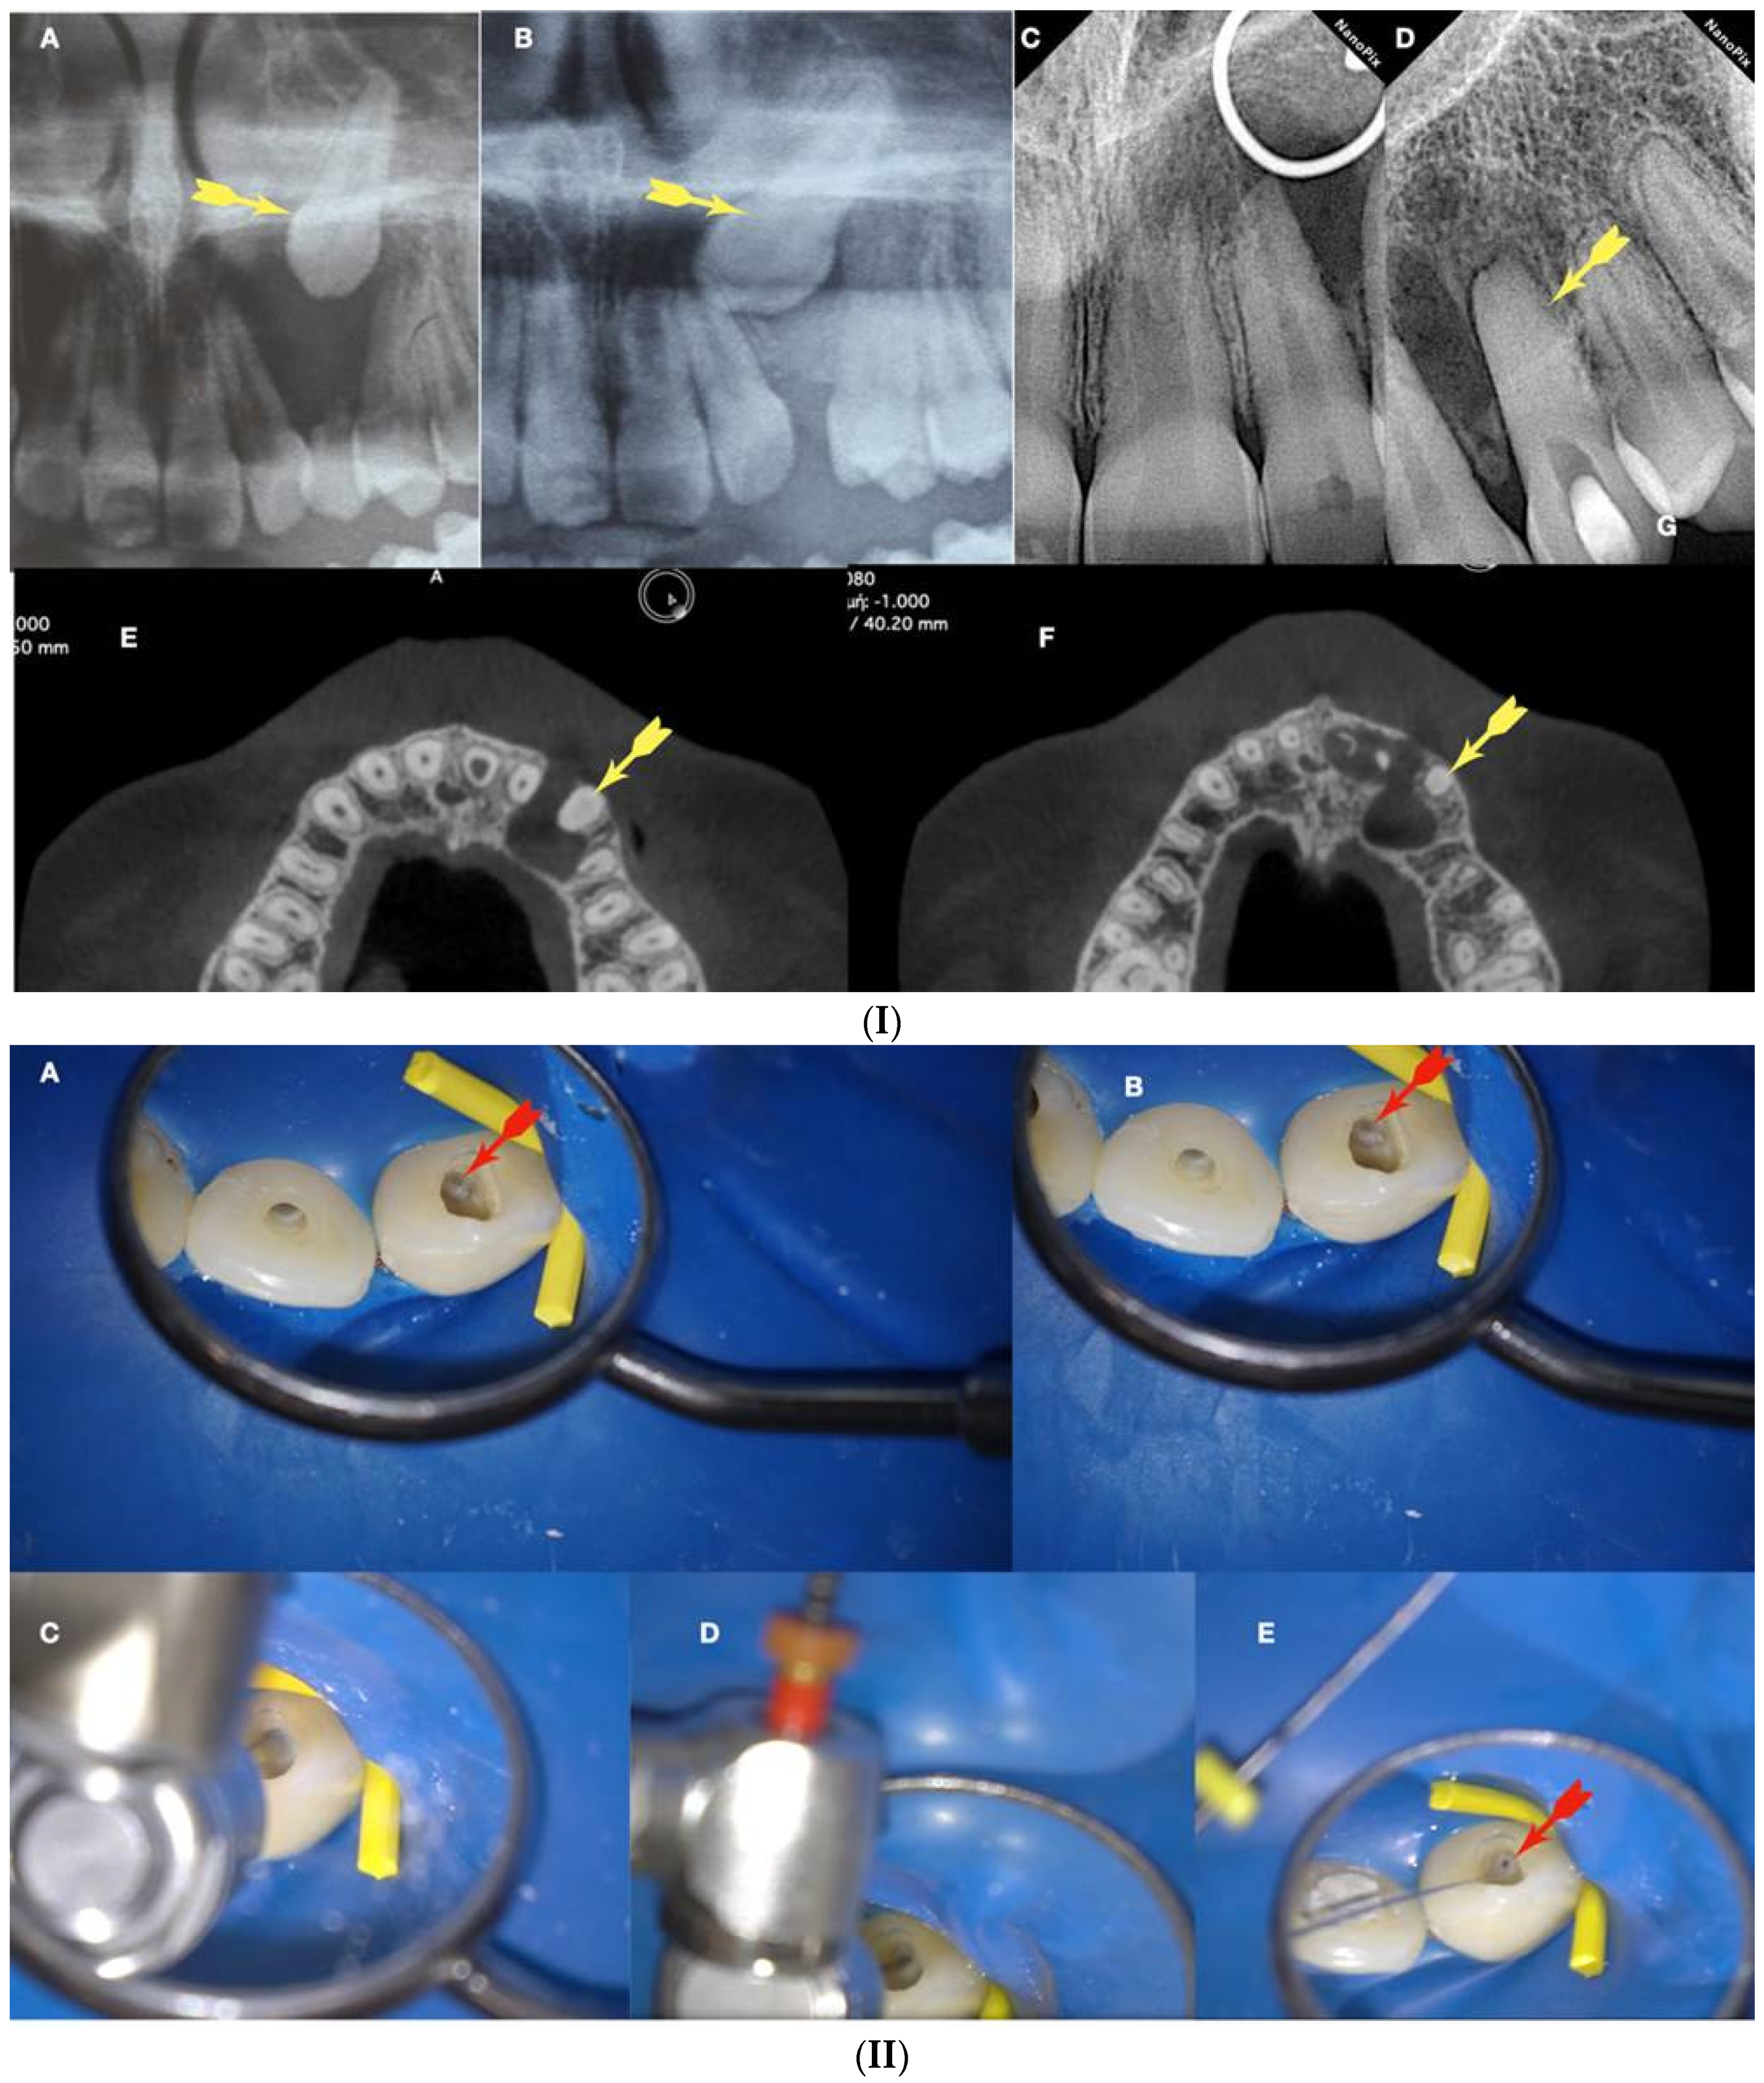

The initial dimple is deepened progressively in a crown-down sequence until a patent pathway is met and confirmed (Figure 9 and Figure 10).

Figure 10.

Buckling resistance activation test (BRAT) negotiation of calcified canals graphic explanation (A). Long-shafted bur access cavity preparation (B). Continuous chelation concept irrigation and D-finder negotiation test (C). Long-shafted access bur of smaller diameter insertion without activation (tactile feedback) (D). Single-stroke activation of the bur (Tactile Controlled Activation) (E). Continuous chelation concept irrigation and D-finder negotiation test. If there is no negotiation, continue to the next step (F). EDM or Active tip file placement inside the access dimple without activation (G). Activation of the EDM file at 500 rpm/3 NCM and application of vertical axial pressure against the calcified canal entrance (long press release twice) (H). Continuous chelation concept irrigation and D-finder negotiation test. If there is no negotiation, continue to the next step (I). EDM or Active tip file placement deeper inside the dedicated access dimple without activation (J). Activation of the EDM file at 500 rpm/3 NCM and application of vertical axial pressure against the calcified canal entrance (long press release twice). As the file goes deeper inside the root, the buckling resistance of the file increases because the lateral walls will not allow the file to buckle and succumb. The axial pressure is transported to the file tip, allowing the file to penetrate (K). Continuous chelation concept irrigation and D-finder negotiation test. If there is no negotiation, continue to the next step (L). EDM or Active tip file placement deeper inside the dedicated access dimple without activation (M). Activation of the EDM file at 500 rpm/3 NCM and application of vertical axial pressure against the calcified canal entrance (long press release twice) (N). Continuous chelation concept irrigation and D-finder negotiation test (O,P). If there is no negotiation, repeat the previous steps. Horizontal light blue arrows: file is engaged in the lateral canal walls, vertical black arrows: direction and force of file movement, Blue drops: irrigation.

As the instrument goes deeper inside the blocked root canal, the buckling resistance of the instrument increases because the lateral canal walls will not allow the instrument to buckle. Any axial pressure applied will be transported to the file tip.

Buckling resistance activation test (BRAT) negotiation is defined as the activation of an engine-driven file with an active or dynamic tip against the conditioned calcified tissue that is blocking the canal trajectory (Figure 9 and Figure 10). The tip of the engine-driven instrument is attached to the calcification point without activation. The instrument is activated according to the manufacturer’s instructions, and the file is pushed in an axial direction against the calcification (long press and release). The lateral buckling movement of the file is restrained by the canal walls. When the progression of the file is achieved, the file is removed from the canal, and the canal is checked for patency with a hand file. If patency is achieved, then standard root canal treatment procedures can be continued. If there is no patency, the same procedure can be attempted deeper inside the calcification. The step-by-step progression of a rotary file through the calcification with the BRAT technique is described in Figure 10.

In Figure 11, Figure 12, Figure 13 and Figure 14, initial negotiation through the calcified canal orifices was carried out using the BRAT technique until canal patency was met. The conditioning of the calcified tissue blocking the canals for the BRAT technique to be effective is preferably accomplished with the continuous chelation concept.